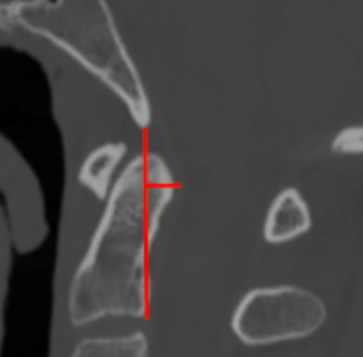

Image Type Cervical Spine X-Ray CT Scan MRI Scan Atlantodental Interval (ADI) Basion–Axial Interval (BAI) Basion–Dens Interval (BDI) Canal Occupying Ratio (COR) Clivo-Axial Angle Facet Joint Overlap (Percent Overlap Method) Facet Joint Step-Off/Dislocation Grabb-Oakes Measurement (pB - C2 line) Occipital Condyle–C1 Interval (CCI) Posterior Atlantodental Interval (PADI) Power’s Ratio Sagittal Vertical Axis (SVA) Segmental Angle Translation on Sagittal Reconstruction